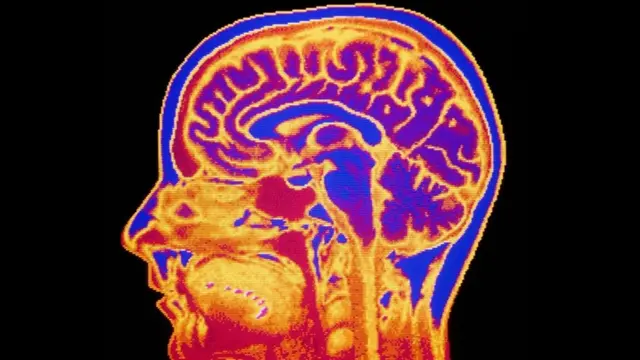

¿Puede explicarse el cerebro humano usando física cuántica?

El eterno acertijo de la consciencia incluso ha llevado a algunos investigadores a invocar a la física cuántica para explicarla.

La noción siempre ha provocado escepticismo, pues no suena sensato explicar un misterio con otro. Pero hay una relación entre la mente y la teoría cuántica desde casi el comienzo.

Aunque muchos la ridiculizan viéndola como charlatanería mística, la "consciencia cuántica" se niega a desaparecer.

Ahora hay físicos que sospechan que, independientemente de si la consciencia influye sobre la mecánica cuántica, esta parte de la física puede ser necesaria para entender completamente cómo funciona el cerebro.